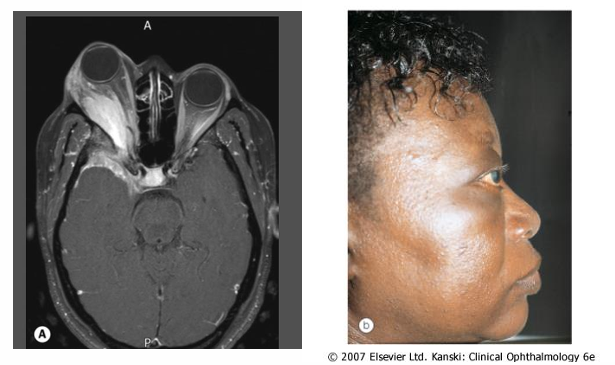

Aneurysms Affecting the Optic Chiasm

Internal Carotid Aneurysms:

Can cause chiasm compression on one side, which may lead to displacement towards the opposite internal carotid artery.

The lateral sides of the chiasm contain axons from the retina temporal to the fovea continuing uncrossed.

Resulting field defect is termed binasal hemianopia, typically worse on the side where the aneurysm resides.